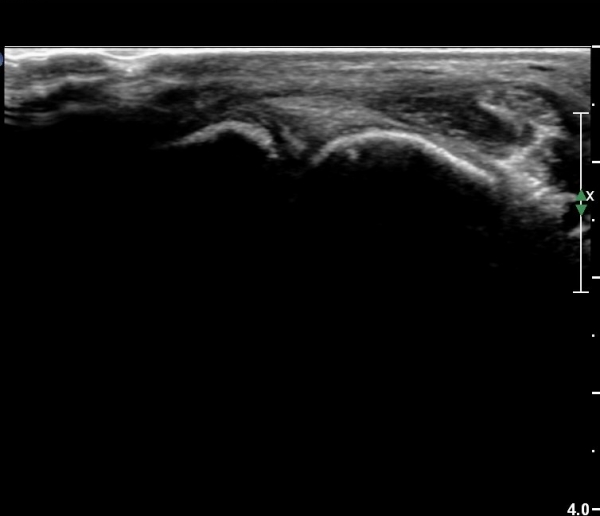

Àü¹æ °æ°ñºñ°ñÀδë Á¾´Ü¸é°Ë»ç¿¡¼­ ƯÀÌ ¼Ò°ßÀ» º¸ÀÌÁö ¾Ê´Â´Ù(»çÁø 3).

¹ß¸ñ°üÀý ¾ÕÂÊ Á¾´Ü¸é°Ë»ç¿¡¼­ °üÀý³» ¼ö¾×Àú·ù°¡ »ç¶óÁö°í(»çÁø 1),